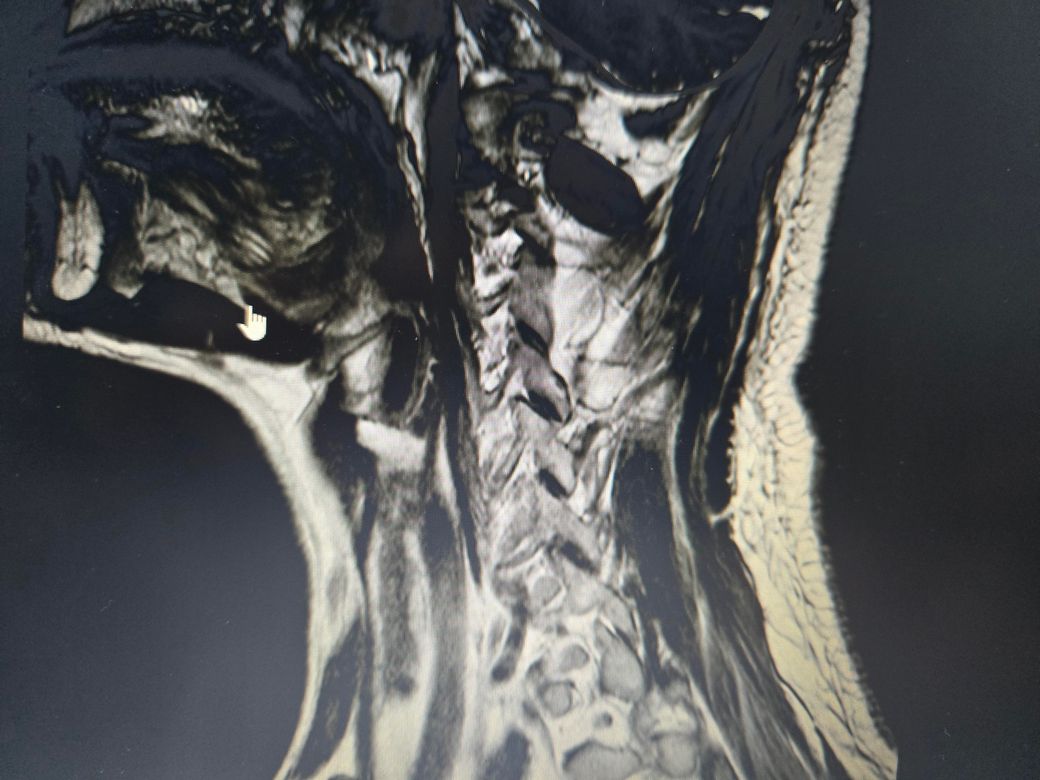

목디스크, 협착증 수술안해도되는건가요

목디스크 협착

정형외과에서는 디스크 협착증소견을 내고서는 마사지 잘하면된다는데, mri상으로도 심하지 않은건지궁금합니다

• 2번 째 사진